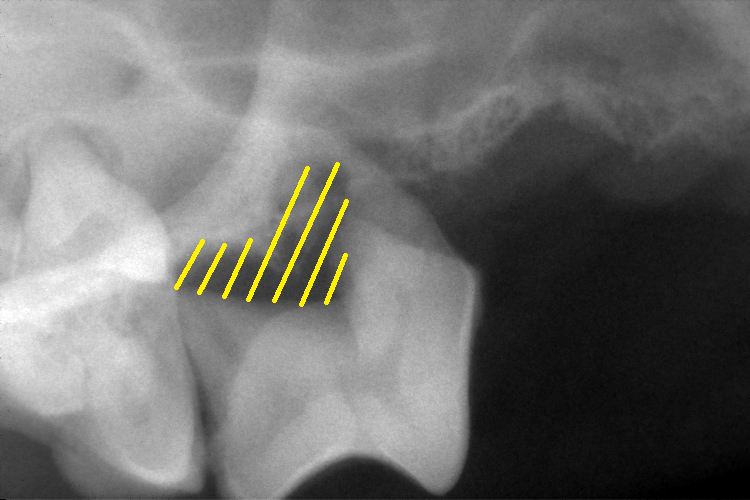

歯科レントゲン

右上顎第4前臼歯と右下顎第4前臼歯です。

黄色斜線部分の歯槽骨が溶け、黒く抜けているのが確認できます。